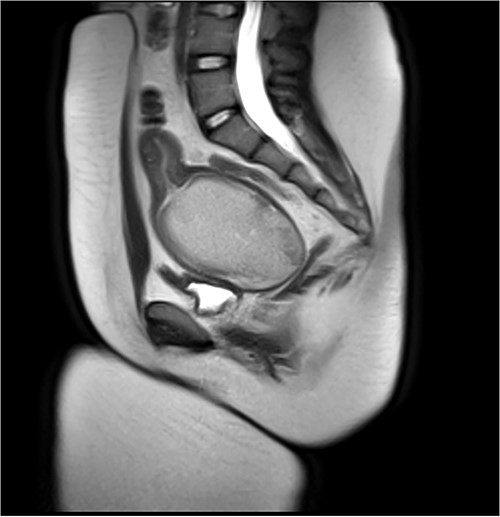

Attempt was made to perform US-guided drainage in IR using largest bore drain (12F) but the HMC had organized into a large clot and was too thick for drainage. Four mg of TPA was then injected into the HMC to allow breakdown of the clot, after which 300 ml of blood was successfully drained (Fig. 2).

Pre-vaginoplasty MRI- Image was taken after IR drainage and suppression to allow distension pre-vaginoplasty.

She remained suppressed and without pain. She discontinued the norethindrone acetate 2 months prior to surgery to allow re-accumulation of the HMC. The surgical team was prepared to perform a buccal graft vaginoplasty, but sufficient mobilization of the native vaginal tissue allowed for an uncomplicated vaginoplasty without graft. A uterine tamponade balloon was placed and expanded with 180 ml of sterile water. Postoperatively she was admitted with a uterine tamponade balloon and urinary catheter in place. These were removed on postoperative Day 5, and she was discharged home on doxycycline and metronidazole for a 7-14 day course and 25 mm stent at night for 14 days. Subsequent vaginoscopy revealed a normal upper vagina and well-healing suture line, able to accommodate a 25 mm rectal dilator (Fig. 3). At the time of writing, she is 5 months postoperative and using the stent a few times a month.